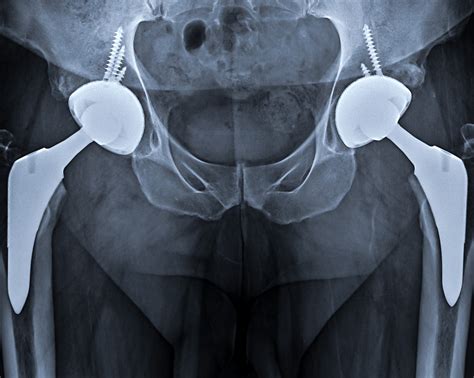

Hip Implant X Ray

Hip implants have revolutionized the field of orthopedics, providing relief and improved mobility for countless individuals suffering from hip joint issues. One of the critical aspects of managing hip implants is the use of hip implant X-ray imaging. This diagnostic tool plays a pivotal role in the pre-operative planning, post-operative monitoring, and long-term management of hip implants. Understanding the importance and process of hip implant X-ray imaging can help patients and healthcare providers make informed decisions.

The Role of Hip Implant X-Ray

Hip implant X-ray imaging is an essential diagnostic tool used to evaluate the condition of the hip joint and the implant itself. It provides detailed images that help orthopedic surgeons assess the alignment, positioning, and integrity of the implant. This information is crucial for both pre-operative planning and post-operative monitoring.